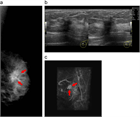

1. 症例の典型例と難渋例を記載した。